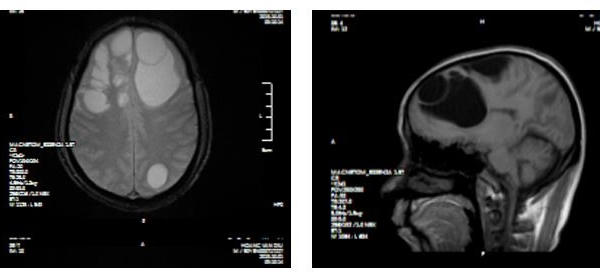

Ổ sán khổng lồ 'lúc nhúc' trong não người đàn ông ở Phú Thọ

Ổ sán khổng lồ cư trú trong não khiến người đàn ông ở Phú Thọ mất dần trí nhớ, phù não diện rộng, phải phẫu thuật khẩn cấp.